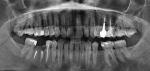

На данный момент нахожусь в Китае, есть сложности в языковом барьере. Беда такая: сломалась стенка жевательного зуба. В стоматологии сделали снимок и вроде, как я поняла сказали, что сделать не могут.

Можете ли Вы подсказать, что можно сделать?

Необходим осмотр и прицельный рентгеновский снимок зуба. 1) Как правило, стенка зуба скалывается, когда жевательный зуб ранее был лечен и восстановлен пломбой больших размеров. И при жевании тонкая стенка не выдерживает нагрузки и скалывается. 2) Если скол произошёл ниже уровня десны – это показание к удалению зуба и восстановлению дефекта имплантом или мостовидным протезом. Если выше уровня десны, тогда эндодонтическое лечение зуба и восстановление его вкладкой и коронкой. Проконсультируйтесь очно со стоматологом-терапевтом.

Нет, так как зуб разрушен до области бифуркации корней. Поэтому такие зубы рекомендуется удалить и восстановить дефект зубного ряда посредством импланта или ортопедической конструкции.

По снимку можно сказать, что нет здоровых твердых тканей коронковой части зуба для последующего восстановления. Если при визуальном осмотре обнаружено много размягченного деминерализованного дентина, тогда это показание к удалению зуба. После дефект можно заместить имплантатом. Проконсультируйтесь очно со стоматологом-хирургом.